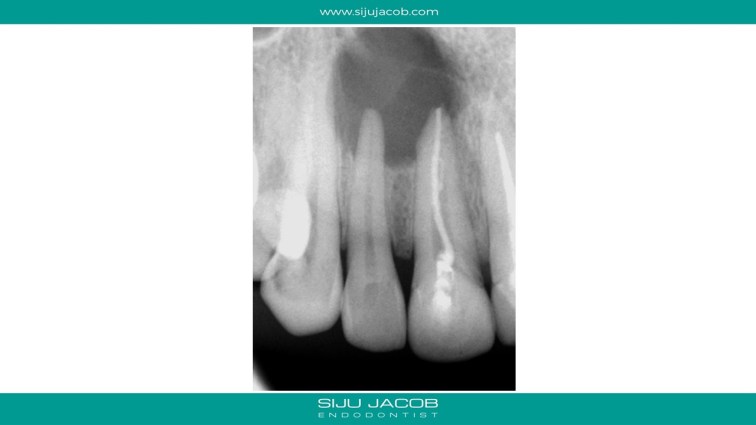

This patient had a large lesion in the right maxillary anterior region. The lateral Incisor tested vital. I decided to re-treat only the central Incisor. Despite several calcium hydroxide changes spread over 2 months, there was persistent drainage of pus. Instead of opting for the more radical option of endo on the lateral and immediate surgery, we decided to do decompression. The drainage stopped and the tooth was subsequently obturated. Patient recently came for some other work and I took a 5-year recall raiograph. It seems to be holding on for now. I was tempted to do the endo on the lateral on several occasions, but it always tests vital.